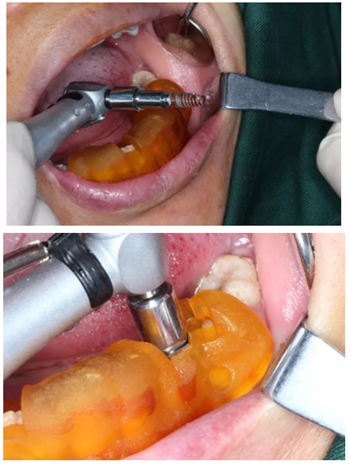

3.根據(jù)手術(shù)計(jì)劃書,使用術(shù)前所設(shè)計(jì)好的長度、直徑的一系列鉆針在導(dǎo)板的引導(dǎo)下進(jìn)行備孔。

4.在全程導(dǎo)板的引導(dǎo)下,使用全程導(dǎo)板工具盒中的攜帶器,從導(dǎo)板套環(huán)孔處將植體植入,直至攜帶器的六角、與導(dǎo)板套環(huán)的六角嚴(yán)絲合縫(如圖,六角對(duì)六角),即表示植體就位成功。